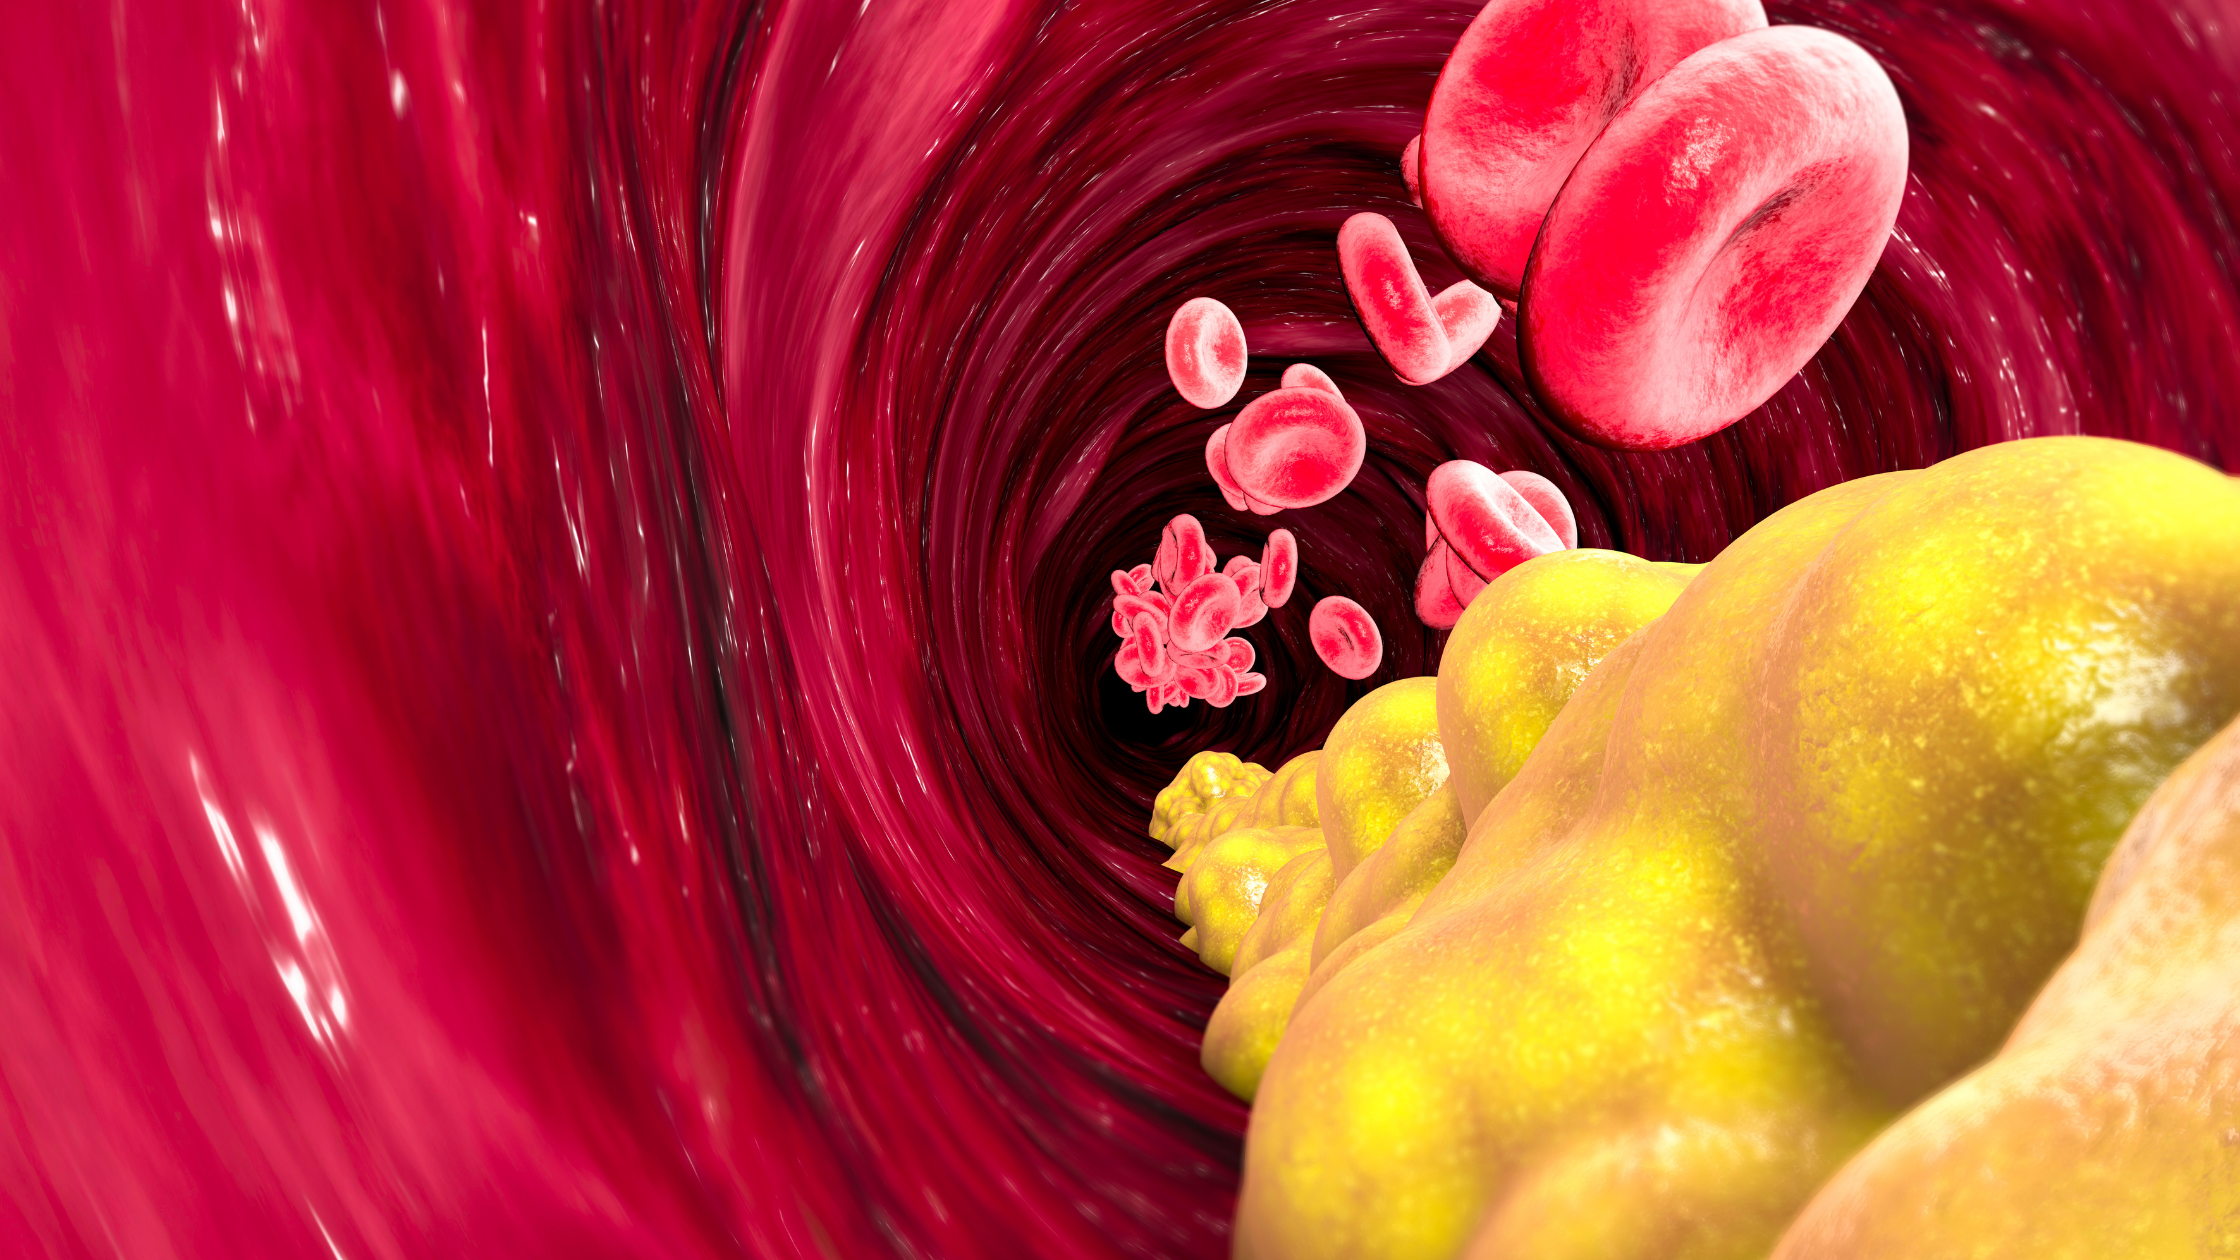

Холестерин в организме: влияние и функции (схемы и диаграммы)